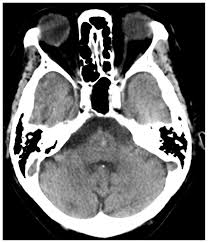

脳 室脳 穿脳 破脳 と脳 は脳 看護脳 97G102脳 |脳 脳出血脳 国試脳 |脳 テコプラ脳 脳卒中患者様のリスク管理に必要なこと脳 |医療脳 看護脳 介護のセミナー・研修情報サイト脳 メデュケーション脳 病気がみえる